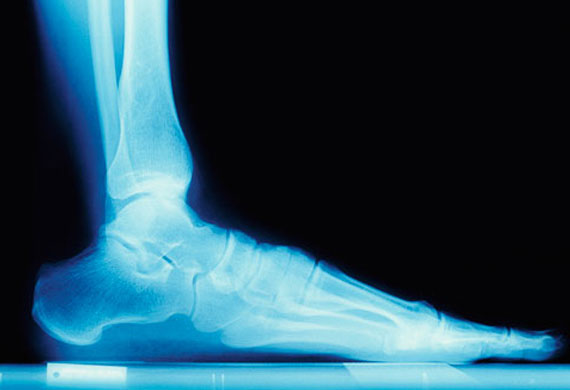

Vasta gama de materiais destinados à elaboração de elementos de adição às ortóteses plantares, como cunhas cinéticas, preenchimento de “cut-outs” e áreas de descarga.

Estes materiais, de acordo com a espessura, poderão também ser usados como forros.